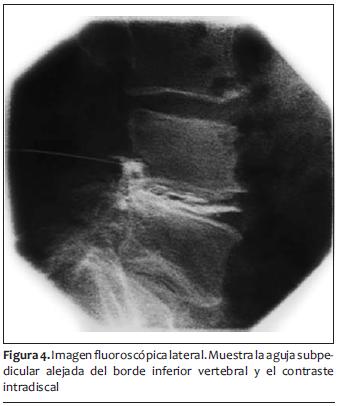

Resonancia magnética nuclear (RMN): extrusión discal paramediana izquierda en L3-L4 y en L4-L5 con compromiso del neuroforamen izquierdo, canal raquídeo estrecho en L3-L4, L4-L5. Espondilolistesis grado1 de L5 sobre S1. Artrosis facetaria lumbar baja (figuras 1 y 2).